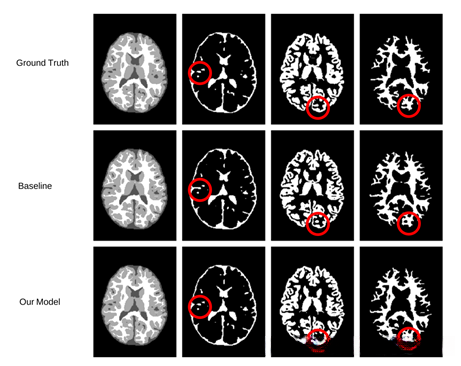

如图所示,该运行段落展示了其分割结果的可视化效果。通过对比标注的区域可以看出,在此过程中我们的模型相较于基线模型捕捉了更多的细节信息。